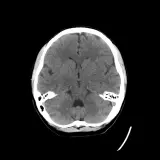

Over 2,100 interactive radiology cases, curated by radiologists for your level of training. Scroll, window, and view cases full screen — just like on PACS. Click linked findings in each writeup to jump straight to them on the image. Cases include sample reports, a focused discussion section, original illustrations, and videos.

Neuro Fellowship — a course tailored for fellows and practicing radiologists with in-depth reviews of advanced neuro topics like brain tumors, featuring rare diagnoses, differentials, and clinical pearls.

PACSで期待されるツールを完備した完全インタラクティブな症例 — スクロール、ウィンドウ調整、ズーム、パン、計測、ROI、フルスクリーンモード。

重要な所見を症例画像上に直接ハイライトする豊富なアノテーション。症例解説内のリンクされた所見をクリックすると、スキャン上の正確な位置へジャンプできます。